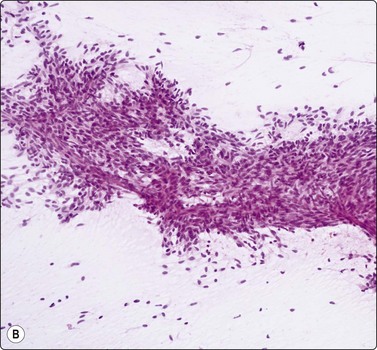

image

Fig. 9.3 Thymoma, lymphoepithelial

Tissue section; biphasic cell population (H&E, HP).

Fig. 9.4 Thymoma, lymphoepithelial; metastatic within lung

Biphasic cell population of lymphocytes and epithelial cells with pale nuclei, small nucleoli and indistinct cytoplasm; note the Hassall’s corpuscle (Pap, HP oil).

In the benign thymomas, the epithelial cells are usually cohesive (Figs 9.1, 9.5) but may also manifest a reduction in intercellular cohesion (Fig. 9.2). Epithelial cells are not immediately evident in the mixed tumors at low power but are discernible using the higher magnification.18,29,30 The epithelial cells are polygonal, oval, or spindle shaped with uniform to slightly irregular nuclear outlines possibly with cleaved or folded nuclei. Their nuclear chromatin is homogeneous, finely distributed and pale and, occasionally, small nucleoli are seen. Cell borders are indistinct, but nuclei are separated by moderate amounts of pale cytoplasm (Figs 9.2, 9.5). In one personally examined case of thymoma metastatic to lung, Hassall’s corpuscles were evident in the clumps of tumor cells (Fig. 9.4); this is a most unusual manifestation and will not be present in most thymomas. When there is a lymphoid population, the bimodal pattern enables one to make a virtually certain diagnosis.18,29,30 In pure epithelial or spindle cell forms, definitive diagnosis is more difficult, although in Dahlgren’s series29 most thymomas were diagnosed and in Tao’s 37 cases30 all FNAC diagnoses of thymoma were verified histologically. Ali and Erozan34 were able to diagnose all of their 14 cases using a combination of cytology, immunocytochemistry and clinical information, and Shin and Katz showed a high accuracy in a range of mediastinal lesions including 14 thymomas.35 Tao and others describe more variation in the degree of cohesion than we have seen, particularly in pure epithelial/nonspindle cell types.30 Overall, the most challenging and the most common in our experience are the lymphocyte-rich (type B1) thymomas, as the tumor cells may be obscured by the lymphocytes.